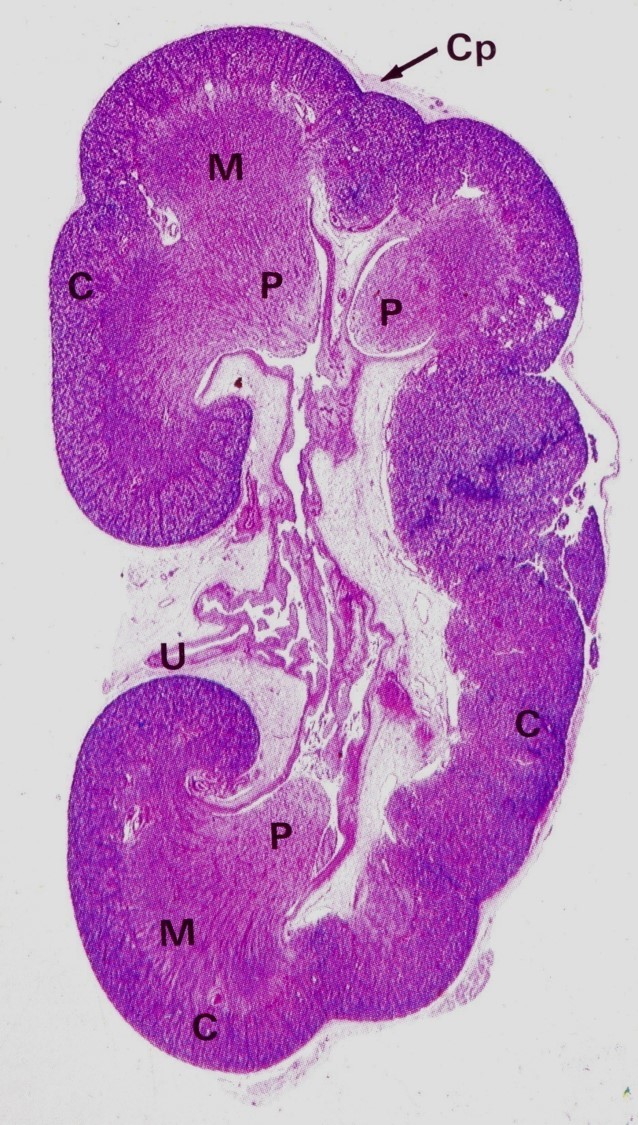

Cp – capsule

C – renal cortex

M – renal medulla

P – renal papilla

U – ureter